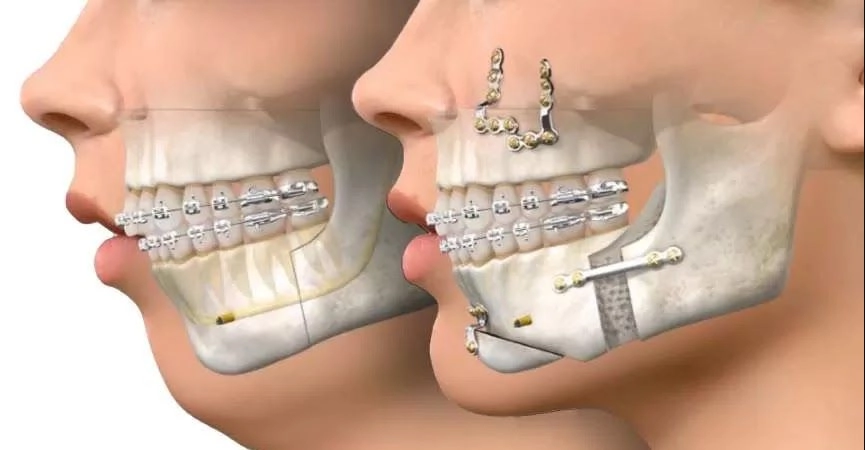

A cirurgia ortognática é um procedimento cirúrgico que reposiciona os ossos da maxila e mandíbula para corrigir deformidades dentofaciais. Vai muito além da estética: restaura funções essenciais como mastigação, respiração e fala.

O procedimento corrige problemas de mordida (má oclusão), assimetrias faciais, prognatismo (queixo projetado), retrognatismo (queixo retraído) e outras alterações ósseas que comprometem tanto a função quanto a aparência facial.

A cirurgia ortognática é um procedimento complexo e meticulosamente planejado, realizado em ambiente hospitalar sob anestesia geral. A duração varia de 2 a 4 horas, dependendo da complexidade do caso.

O reposicionamento ósseo corrige simultaneamente a mordida e harmoniza o rosto, proporcionando equilíbrio entre terço médio e inferior da face.

A cirurgia ortognática é um procedimento complexo e meticulosamente planejado, realizado em ambiente hospitalar sob anestesia geral. A duração varia de 2 a 4 horas, dependendo da complexidade do caso.

O reposicionamento ósseo corrige simultaneamente a mordida e harmoniza o rosto, proporcionando equilíbrio entre terço médio e inferior da face.